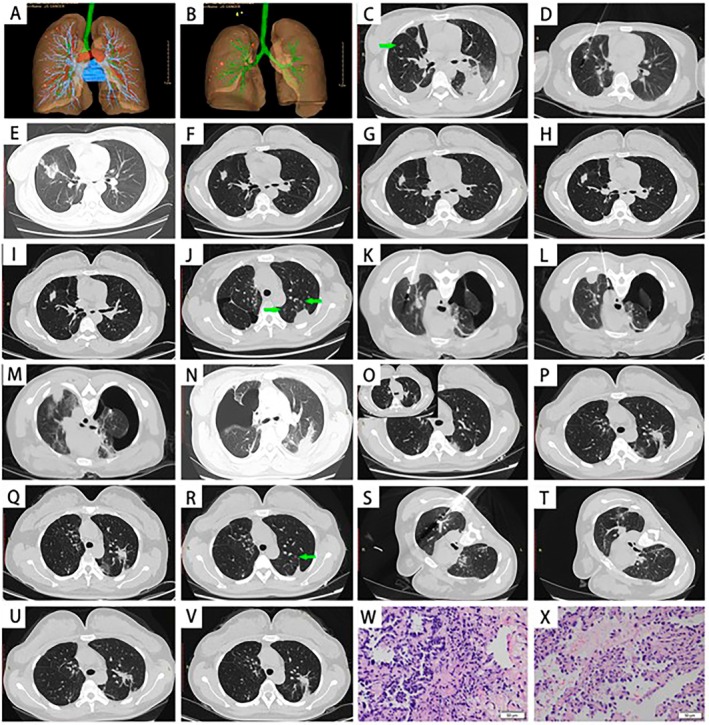

背景:多发磨玻璃混浊(mGGOs)常见于早期肺腺癌患者。对于这些mggo最适当和有效的治疗方法仍然存在争议。本研究的目的是回顾性评价视频辅助胸外科手术(VATS)联合计算机断层扫描(CT)引导微波消融(MWA)治疗同步多发原发性肺癌(sMPLC)的有效性和安全性,并证明我院的长期手术效果。材料和方法:2019年4月至2021年12月,我们招募了47例接受VATS联合ct引导下MWA治疗mGGOs的患者。从外科数据库和电子病历中精心提取有关入选受试者的综合数据,包括临床特征、影像学表现、组织病理学特征和手术记录。本研究评估的结果包括联合治疗的可行性和安全性,以及无事件生存期(EFS)、局部无进展生存期(LPFS)和总生存期(OS)。结果:共有47例以mGGOs为特征的sMPLC患者行VATS联合ct引导MWA。在该队列中,173个ggo被切除,其中69个(39.9%)结节大于8 mm, 104个(60.1%)结节在5 - 8 mm之间。我们记录了83个结节的58种VATS手术。此外,90例继发性结节在单次住院或多次住院期间(从1到4次)接受ct引导下的MWA治疗。我们在47例患者中取得了100%的技术成功率。随访期间,47例患者无局部肿瘤进展或复发。3年无事件生存率为100%,5年生存率为66.82%,5年总生存率为97.5%,仅有1例患者死于非相关原因。结论:VATS联合ct引导下MWA治疗mggo是一种安全有效的方法。这种结合标志着外科医生可以同时使用针和手术刀的时代的开始。

Results: A total of 47 patients with sMPLC characterized by mGGOs underwent VATS combined with CT-guided MWA. In this cohort, 173 GGOs were removed, including 69 nodules (39.9%) larger than 8 mm and 104 nodules (60.1%) measuring between 5 and 8 mm. We recorded all 58 types of VATS surgeries performed on 83 nodules. Additionally, 90 secondary nodules were treated with CT-guided MWA during either a single hospitalization or multiple hospitalizations (ranging from 1 to 4). We achieved a 100% technical success rate among the 47 patients. During the follow-up, there was no local tumor progression or recurrence among the 47 patients. Event-free survival was 100% at 3 years and 66.82% at 5 years, and the 5-year overall survival rate was 97.5%, with only one patient dying from an unrelated cause.